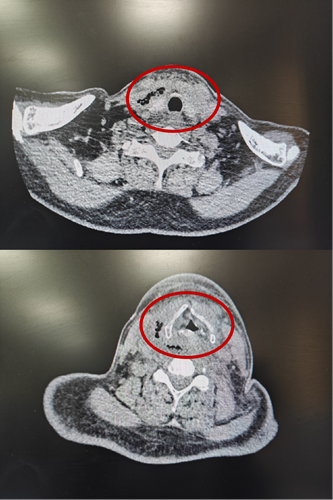

2月15日与20日,当整座城市沉浸在辞旧迎新的欢声笑语中,两位病情凶险的颈部深部脓肿患者先后被推入耳鼻咽喉头颈外科。他们都有多年糖尿病病史,春节期间饮食不规律、作息紊乱、血糖波动大,让原本隐匿的感染如野火般迅速蔓延。其中一位患者的感染已突破颈部间隙,如藤蔓般向下侵入纵隔区域——那里是心脏、大血管、气管的“交通枢纽”,是人体最脆弱的生命禁区之一。CT影像上,脓肿中密布的气腔像一个个危险的信号,气管被严重受压,每一次呼吸都变得艰难。文献数据冰冷而沉重:颈深部脓肿并发下行性纵隔炎,病死率高达40%~70%。时间,从未如此紧迫。

患者甲CT示:颈部及纵隔脓肿,脓肿中含有多个气腔